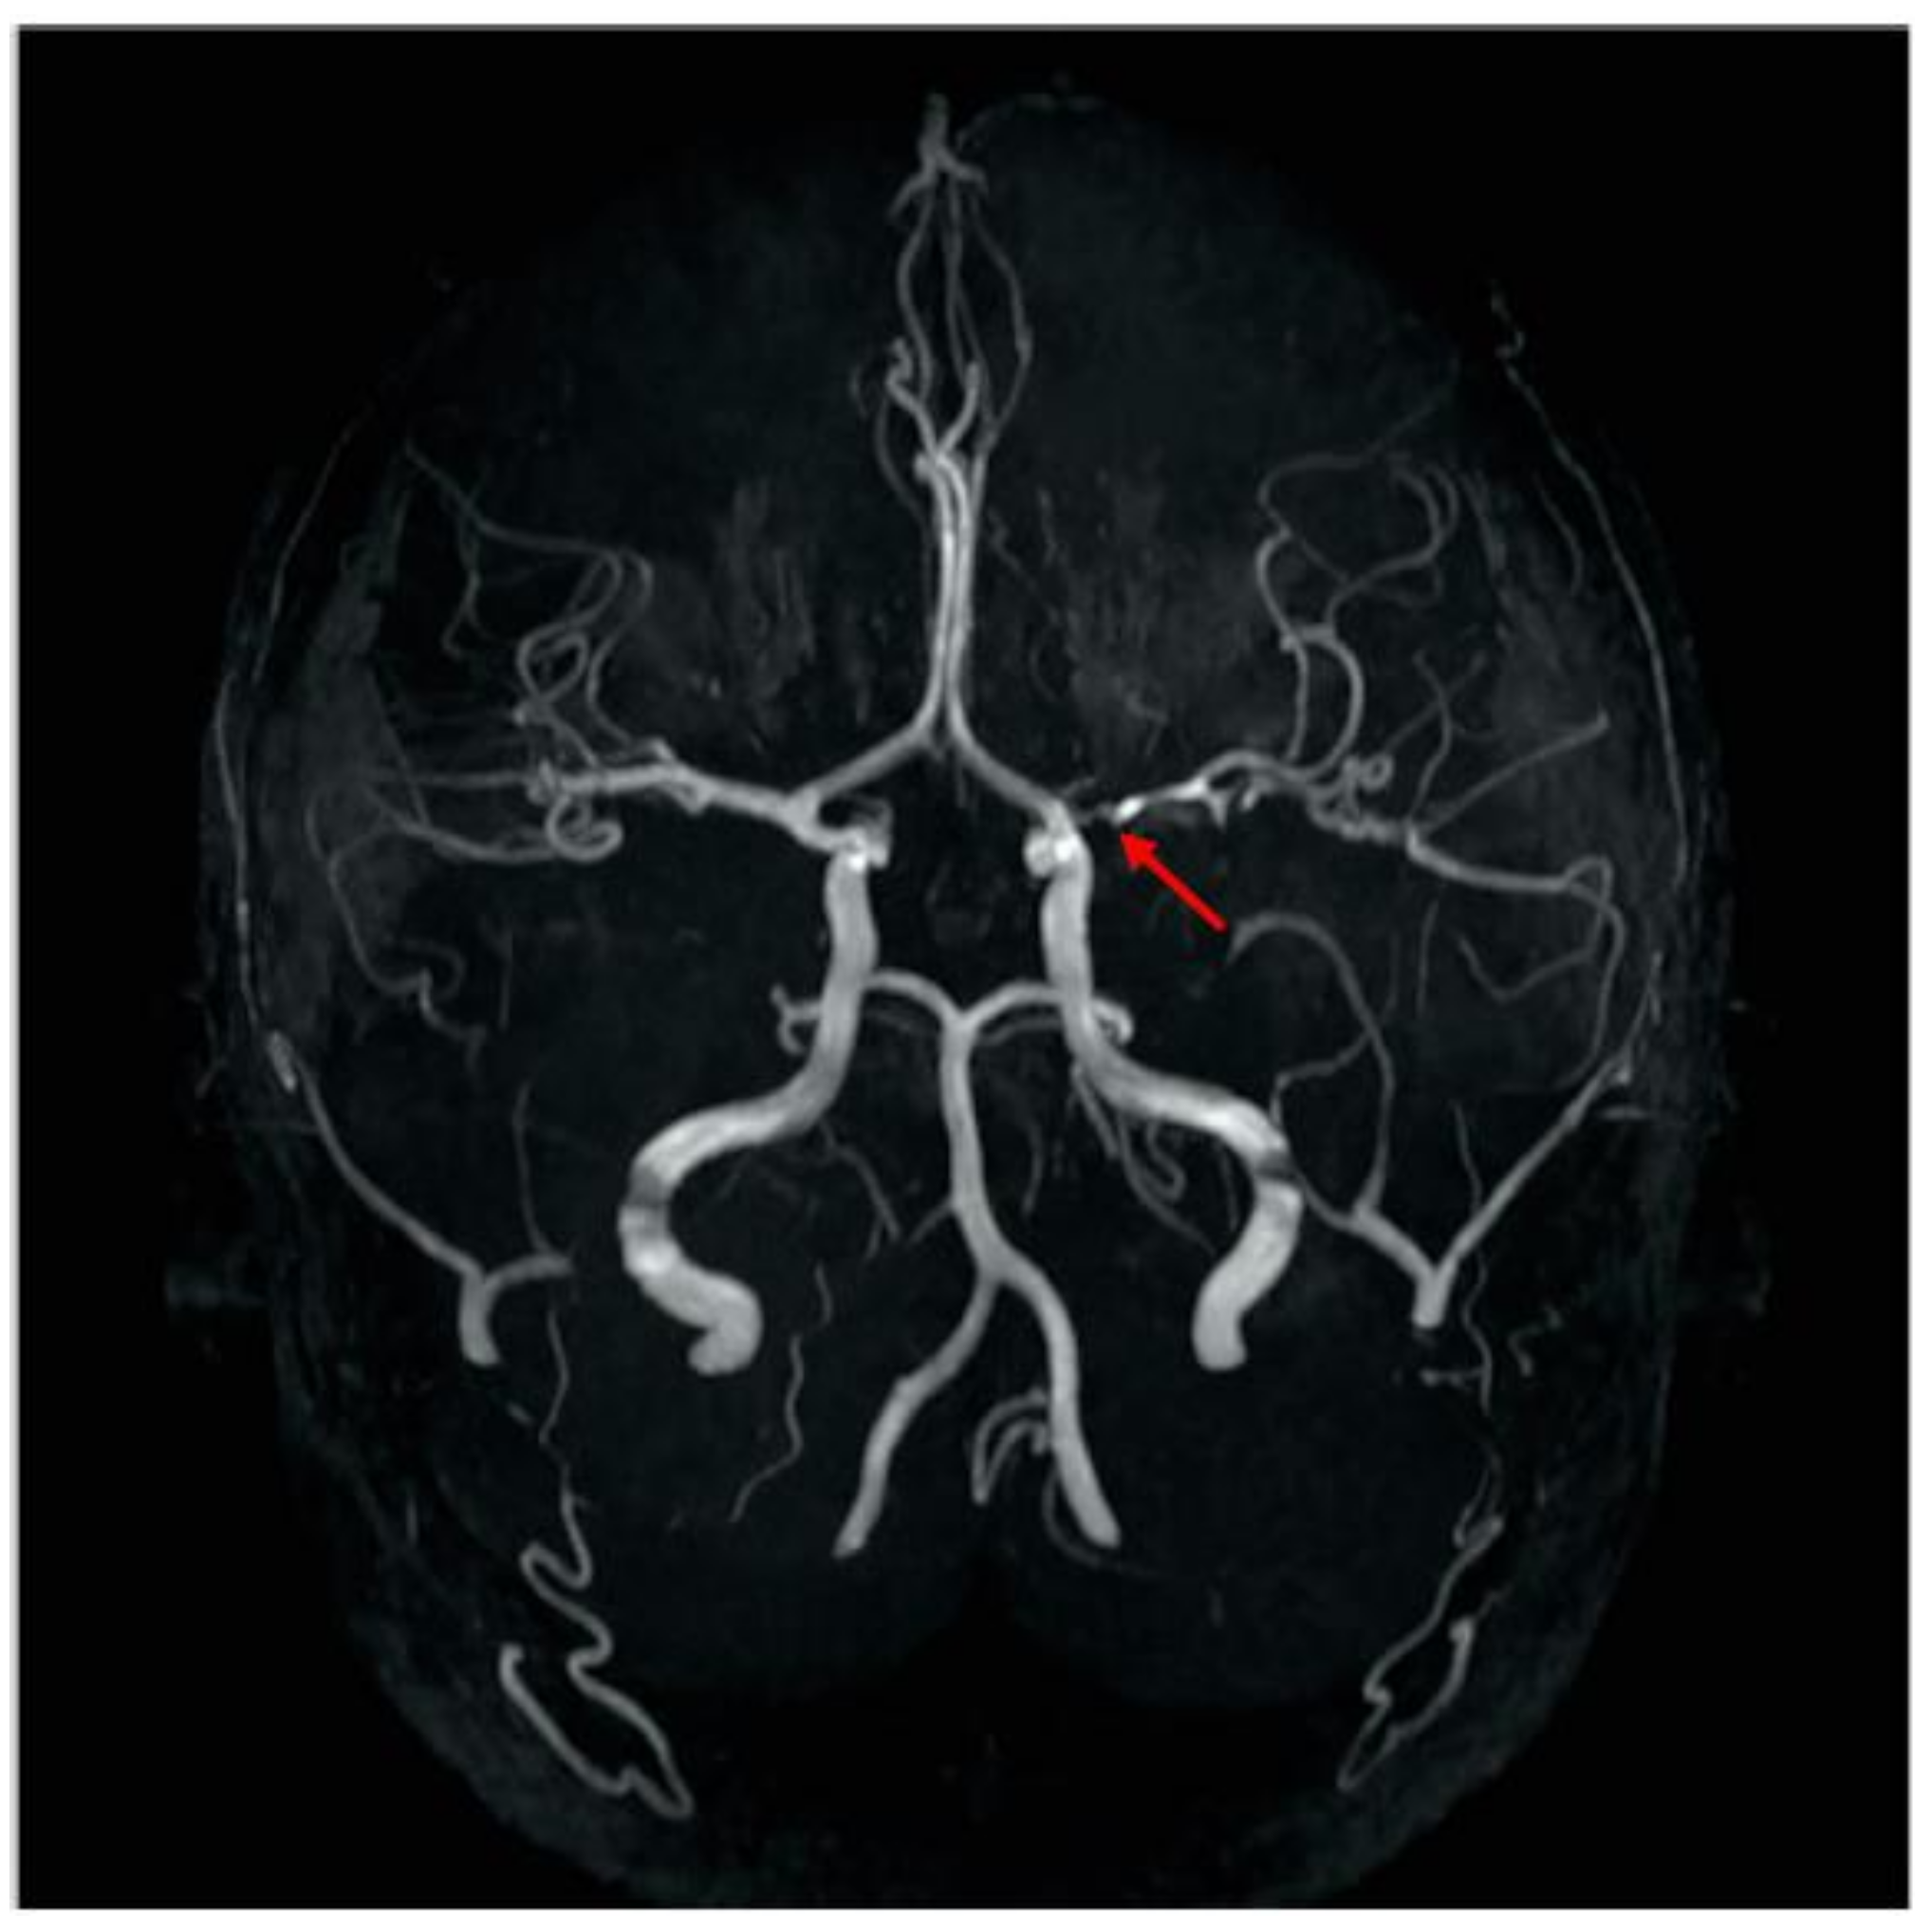

2. Patient Description

| Baumgartle * | 2016 | M/12 years old | Headache, facial drooping, slurred speech and right sided weakness | Left MCA infarction |